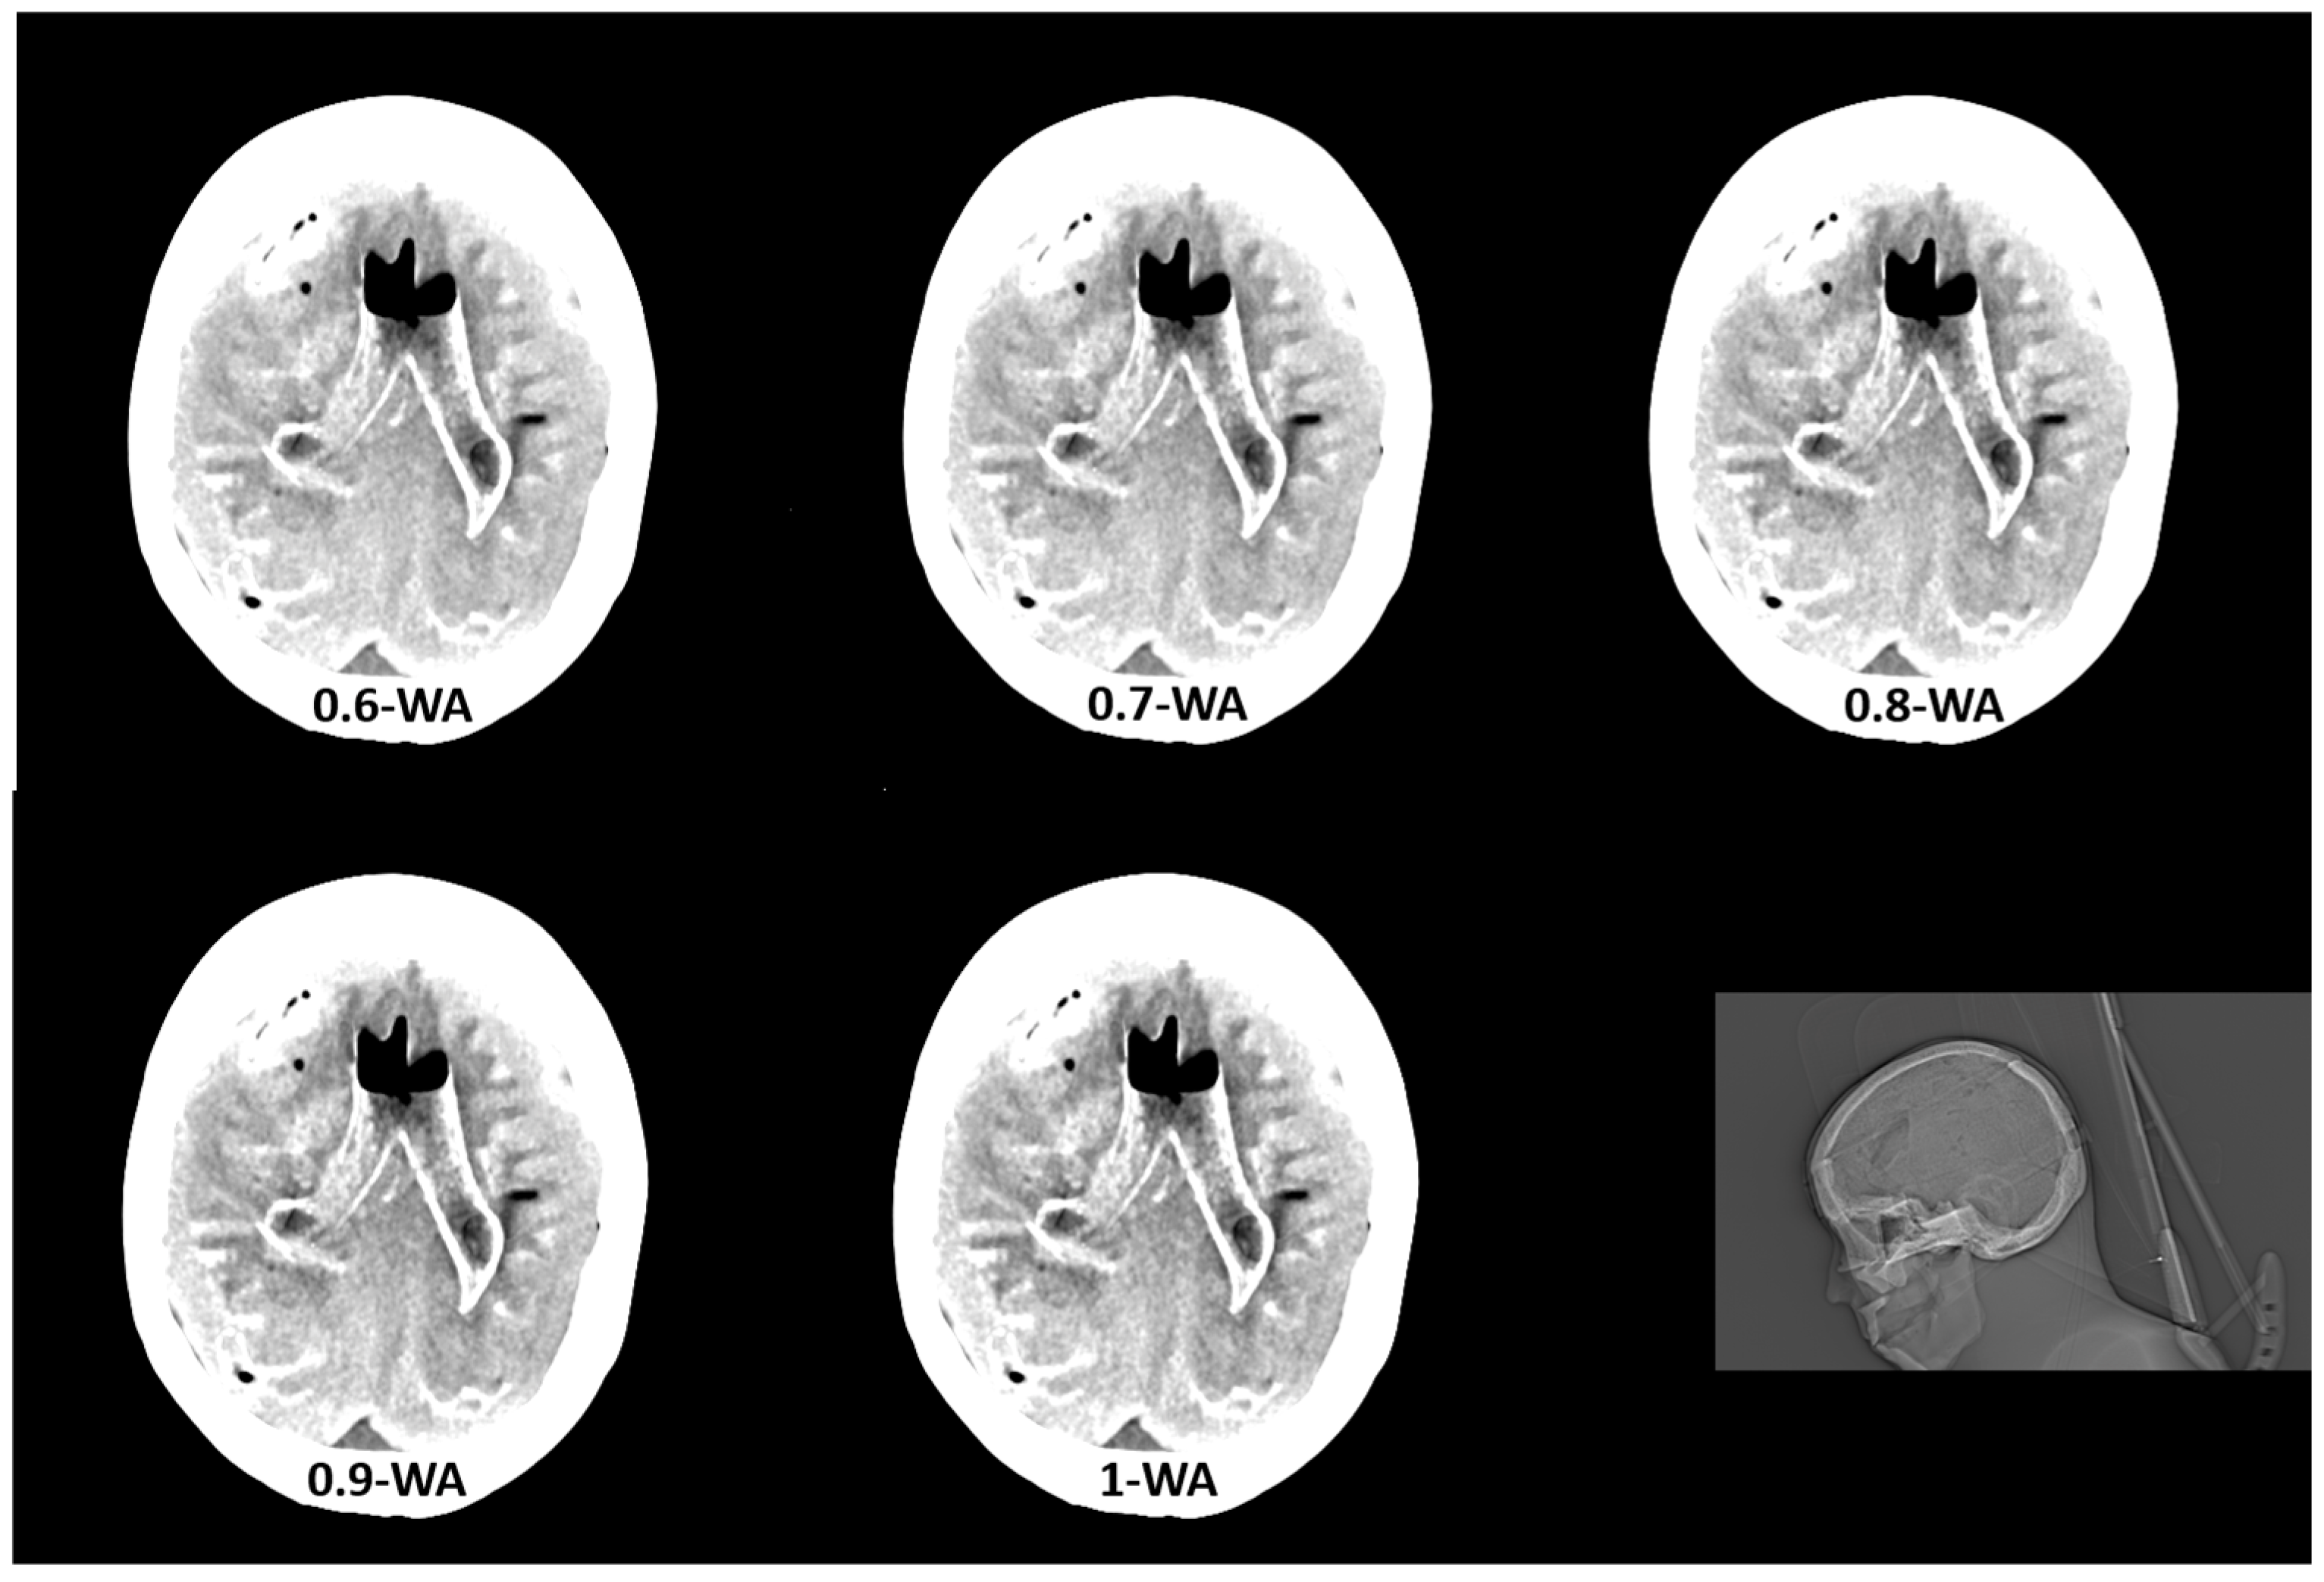

The qualitative assessment of the image quality of the 0.4-WA, 0.6-WA, and 0.8-WA patient reconstructions (Figure 5) was performed according to the methodology described in Section 2.1.3. of the phantom study.

Figure 5.

Weighted average (WA) image datasets of the brain with different weighting factors—0.4 (a), 0.6 (b), and 0.8 (c) of the same patient at the level of the frontoparietal lobe, basal ganglia, and posterior fossa. All images are displayed with the same window width and level (WW 80, WL 35).

The results of the qualitative analysis and image quality scores for all three readers, along with the results of the Friedman test with Bonferroni correction, are summarized in Table 6 and Figure 11. All readers found statistically significant differences in noise, SCA, and PFAI between all three WA image datasets. Reader 1’s results showed no significant differences in GM–WM contrast between the 0.4-WA and 0.6-WA images (p = 0.086), while reader 3 found no significant difference between the 0.4-WA and 0.8-WA reconstructions (p = 0.161). All three readers found that the overall IQ of 0.8-WA images was significantly lower compared to the 0.4-WA and 0.6-WA reconstructions. Two readers rated the overall IQ highest for 0.6-WA, with statistically significant differences compared to 0.4-WA and 0.8-WA (both p < 0.001). Reader 1 found the overall IQ of the 0.4-WA and 0.6-WA reconstructions equally superior to that of 0.8-WA (p < 0.001).

This study shows that the image quality of 0.6-WA image reconstructions is superior to the 0.4-WA images, which are generally recommended for the routine evaluation of non-contrast DECT of the brain. Quantitative and subjective analysis of phantom and patient images revealed that the optimal balance between GM–WM CNR, noise, and artifacts is achieved in WA reconstructions with 60% to 40% contribution of low-energy (80 kVp) and high-energy (140 kVp) datasets, respectively. While SECT provides an acceptable contrast-to-noise ratio, the 0.6-WA DECT reconstructions significantly outperformed the SECT proxy DECT reconstructions with 0.4 WF. This improved contrast between GM and WM increases the diagnostic accuracy of brain imaging, which is not as easily achieved with SECT.

Building on the phantom study, the patient study focused on 0.4-WA, 0.6-WA, and 0.8-WA image datasets. The quantitative analysis showed the same trend as in the phantom study—as expected, GM–WM CNR, SCA, and PFAI increased with higher WF. Although the absolute differences in CNR between the different WA image datasets are small, they are statistically significant and clinically relevant. Even small improvements in CNR can enhance diagnostic confidence, particularly in distinguishing subtle brain pathologies, as the inherent GM–WM contrast on CT imaging is small, with only a 5–10 HU difference in attenuation. Readers agreed that 0.6-WA reconstructions had the highest overall quality for image evaluation. We argue that a slight prevalence of low-energy data enhances GM–WM CNR while the contribution of high-energy data is still high enough to keep the artifacts at a reasonably low level. Although the routinely used 0.4-WA reconstructions, which are considered a proxy for standard SECT images at 120 kV, have fewer artifacts compared to 0.6-WA images, they are diagnostically inferior because they do not achieve sufficient GM–WM CNR, which is pivotal for detecting abnormalities in the brain tissue. On the other hand, although GM–WM CNR is higher in 0.8-WA images compared to 0.6-WA reconstructions, the artifacts affecting the analysis at the brain–bone interface (SCA) and posterior fossa (PFAI) significantly lower its overall diagnostic value. Moreover, all readers deemed 0.8-WA reconstructions to be significantly inferior to 0.4- and 0.6-WA images. These results are consistent with other studies that have shown that radiologists are more likely to prefer higher-contrast images, even at the expense of increased noise, over lower-contrast images with minimal noise artifacts [25,39].